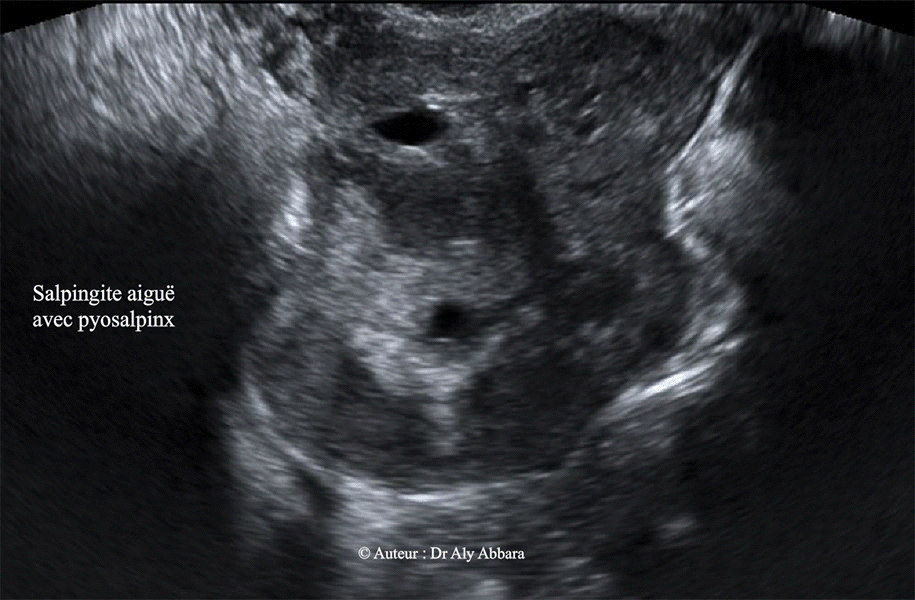

Image animée montrant l'aspect échographique d'une

salpingite aiguë sévère au stade de pyosalpinx

.